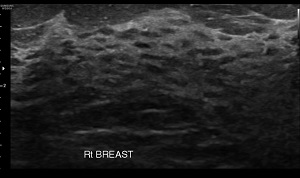

• Findings: Dilatation of ducts with cyst of varying sizes.